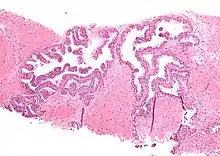

| Micrograph showing high-grade prostatic intraepithelial neoplasia. H&E stain. | |

Microscopically, PIN is a collection of irregular, atypical epithelial cells. The architecture of the glands and ducts remains normal. The epithelial cells proliferate and crowding results in a pseudo-multilayer appearance. They remain fully contained within a prostate acinus (the berry-shaped termination of a gland, where the secretion is produced) or duct. The latter can be demonstrated with special staining techniques (immunohistochemistry for cytokeratins) to identify the basal cells forming the supporting layer of the acinus. In prostate cancer, the abnormal cells spread beyond the boundaries of the acinus and form clusters without basal cells. In HGPIN, the basal cell layer is disrupted but present. PIN is primarily found in the peripheral zone of the prostate (75-80%), rarely in the transition zone (10-15%) and very rarely in the central zone (5%), a distribution that parallels the zonal distribution for prostate carcinoma.[7]